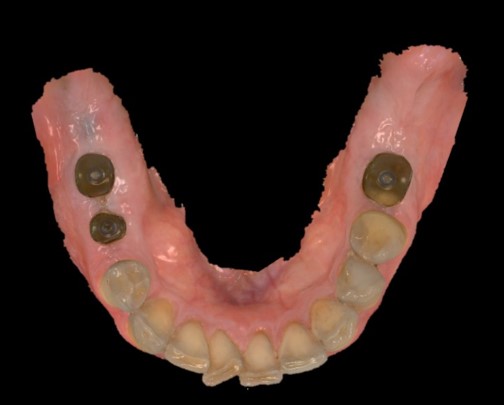

Fig. 2. Scansione intraorale.

Il paziente, in buono stato di salute generale, si presentava con un’edentulia dei settori posteriori dell’arcata mandibolare. In particolar modo, all’esame obiettivo, si evidenziava l’assenza di tutti i molari inferiori e del secondo premolare di destra (Figure 1,2). Il paziente riferiva la perdita degli elementi dentali da qualche anno per motivi di carie e fratture, inoltre diceva di non aver mai provveduto ad una nuova riabilitazione principalmente per mancanza di tempo, a causa dei tanti impegni di lavoro. Si pianificava quindi una riabilitazione implantare degli elementi 45-46 e 36, da eseguire in chirurgia guidata in un’unica seduta, e con l’inserimento di nuovo tipo di abutment di guarigione chiamato Profile Designer iPhysio® (Lyra ETK, Sallanches, Francia) in grado di ridurre i tempi legati alle fasi di protesizzazione degli impianti.